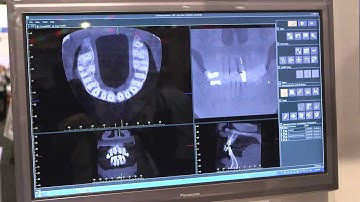

How to use the Veraviewepocs 3D - CBCT - Operation Video